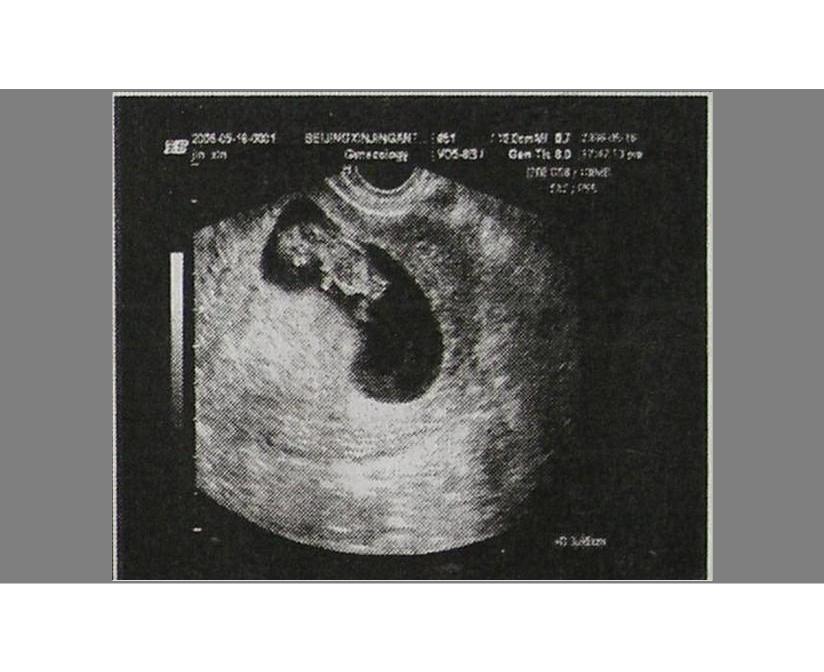

孕妈不放心的话,可以通过B超在宫腔内看到孕囊,随着胚胎不断成长,孕囊内会形成胎芽、胎心,如果孕妈在医院检查时,看得到孕囊,胎心和胎芽,就可以确认为宫内妊娠。

- 孕囊的形状为圆形和椭圆形,看上去清晰可见,就是正常的;

- 在怀孕6周时孕囊直径约2厘米,怀孕10周时约5厘米。

医院会建议孕妇在怀孕42天时去所在地的妇产医院建档,做B超检查,这时候一般会看到完整的孕囊,如果月经不是很规律,可以晚一点去。

一般在42天左右去医院做个B超检查,可以看到完整的孕囊 。